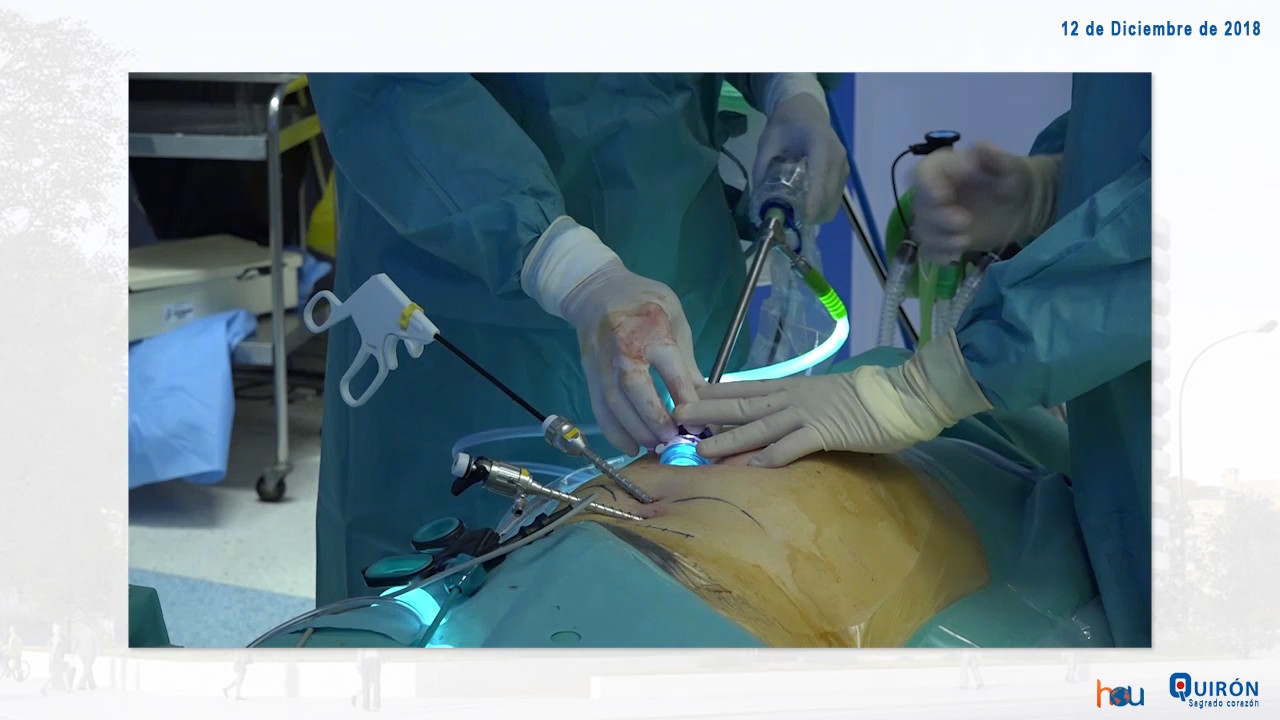

Salvador Morales-Conde M.D | Bilateral Inguinal-Scrotal TEP

Dr Morales demonstrates a bilateral TEP repair for inguino-scrotal hernia, addressing the difficulty of handling large hernia sacs by a totally extra-peritoneal approach. Back [...]